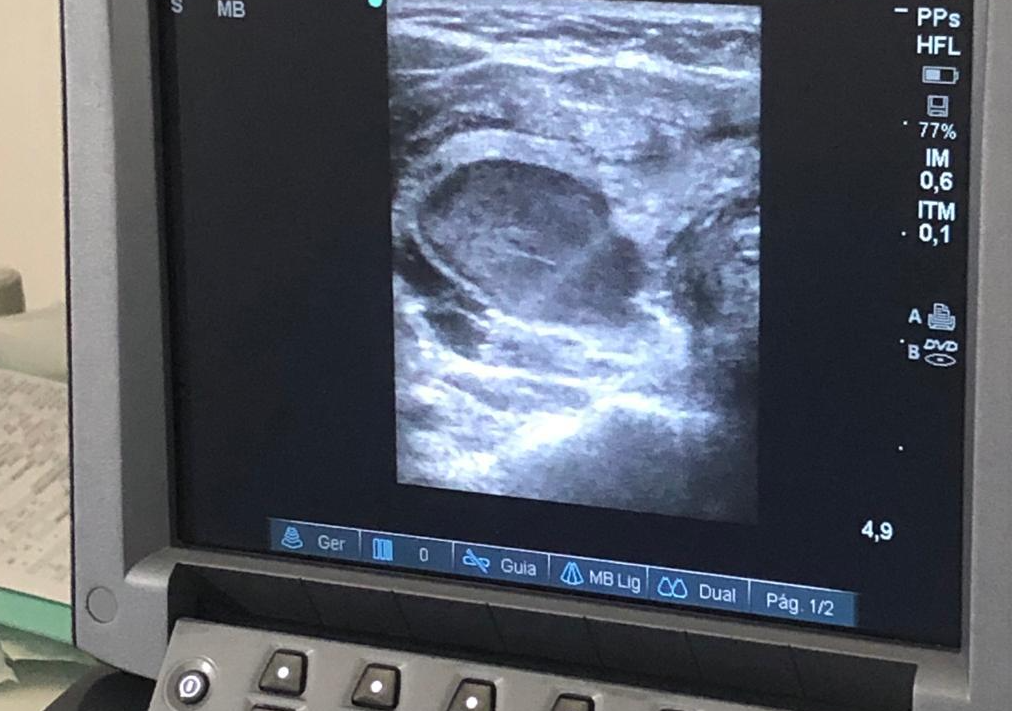

Quando temos um nódulo na tireoide e este nódulo necessita ser tratado, uma das opções de tratamento é a Ablação por Radiofrequência. Diferente de outros tipos de tratamento, como a cirurgia e o iodo radioativo, a Ablação por Radiofrequência é um tratamento que atua somente no nódulo, não afetando o tecido sadio da tireoide. Através de um eletrodo-agulha que é inserido no nódulo, guiado pelo ultrassom (como se fosse numa punção-aspirativa), é gerada pela radiofrequência uma quantidade de calor suficiente para que haja a destruição do nódulo. O nódulo se torna um tecido inerte, que é então absorvido lentamente pelo organismo, num processo que pode durar alguns meses. A área atingida pelo eletrodo agulha é controlada pelo ultrassom, dessa maneira o tratamento por radiofrequência atinge rigorosamente a área do nódulo, não afetando assim o tecido tireoideano sadio. As principais vantagens deste procedimento são: a preservação da função da tireoide, a ausência da necessidade de internação (o paciente permanece no hospital ou clínica entre 3 a 4 hs) e a rápida volta às suas atividades normais (entre 24 e 72 hs).